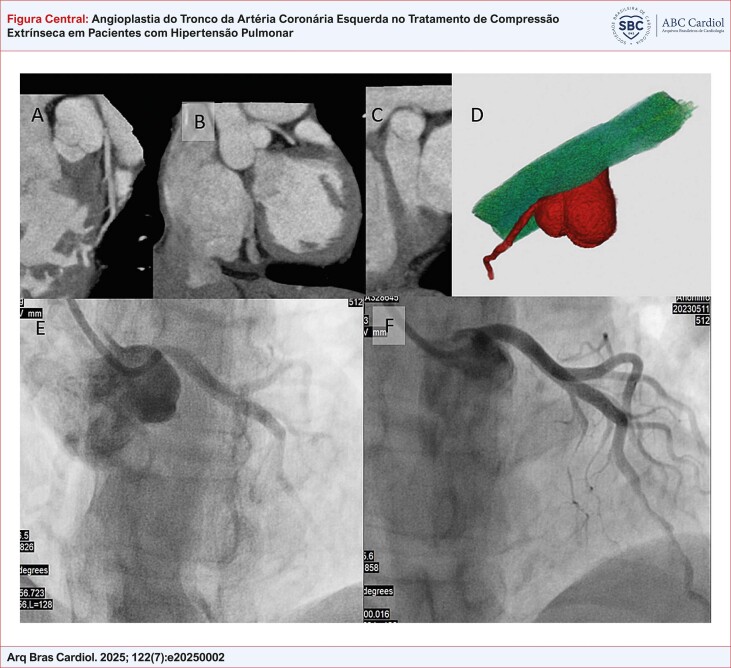

背景:肺动脉高压(PH)最常见的临床表现包括用力性呼吸困难、全身充血和晕厥。心绞痛也可能是一个相关的表现,特别是当左主干冠状动脉(LMCA)被扩张的肺动脉外部压迫时。然而,在这种临床情况下,关于冠状动脉阻塞最合适的诊断和治疗策略仍然存在重大差距。目的:评价冠状动脉成形术联合支架植入术对PH合并LMCA外源性压迫患者症状缓解的可行性及影响。方法:本描述性研究纳入了12例PH患者,这些患者在巴西巴西圣保罗大学医学院医院cora 研究所肺循环门诊接受随访。所有患者均行冠状动脉成形术合并支架植入治疗LMCA外源性压迫。结果:共分析12例患者,平均年龄47.9岁,以1组PH为主,接受特异性治疗。所有的手术都取得了极好的立竿见影的效果,30天后心绞痛得到缓解。在平均33个月的随访期间,无手术相关并发症报告,心绞痛症状得到控制。4名患者死于进行性心力衰竭。结论:研究结果支持冠脉血管成形术作为一种缓解LMCA压迫合并ph患者心绞痛症状的策略的可行性。需要进一步的研究来评估这种干预对硬临床结果的影响,以及在无症状患者中的筛查作用。

Background: The most common clinical presentation of pulmonary hypertension (PH) includes exertional dyspnea, signs of systemic congestion, and syncope. Angina pectoris can also be a relevant manifestation, especially in cases where the left main coronary artery (LMCA) is externally compressed by a dilated pulmonary artery. However, significant gaps remain regarding the most appropriate diagnostic and therapeutic strategies for coronary obstruction in this clinical scenario.

Objectives: To assess the feasibility and impact of coronary angioplasty with stent implantation on symptom relief in patients with PH and extrinsic compression of LMCA.

Methods: This descriptive study included 12 patients with PH who were followed at the Pulmonary Circulation Outpatient Clinic of the Instituto do Coração, Hospital das Clínicas da Faculdade de Medicina da Universidade de São Paulo. All patients underwent coronary angioplasty with stent implantation to treat extrinsic compression of LMCA.

Results: A total of 12 patients were analyzed, with a mean age of 47.9 years, predominantly with group 1 PH and under specific therapy. All procedures achieved excellent immediate results, with angina relief observed at 30 days. During a mean follow-up of 33 months, no procedure-related complications were reported, and angina symptoms remained controlled. Four patients died due to progressive heart failure.

Conclusion: The findings support the feasibility of coronary angioplasty as a strategy for symptomatic relief of angina in patients with LMCA compression associated with PH. Further studies are needed to evaluate the impact of this intervention on hard clinical outcomes, as well as the role of screening in asymptomatic patients.